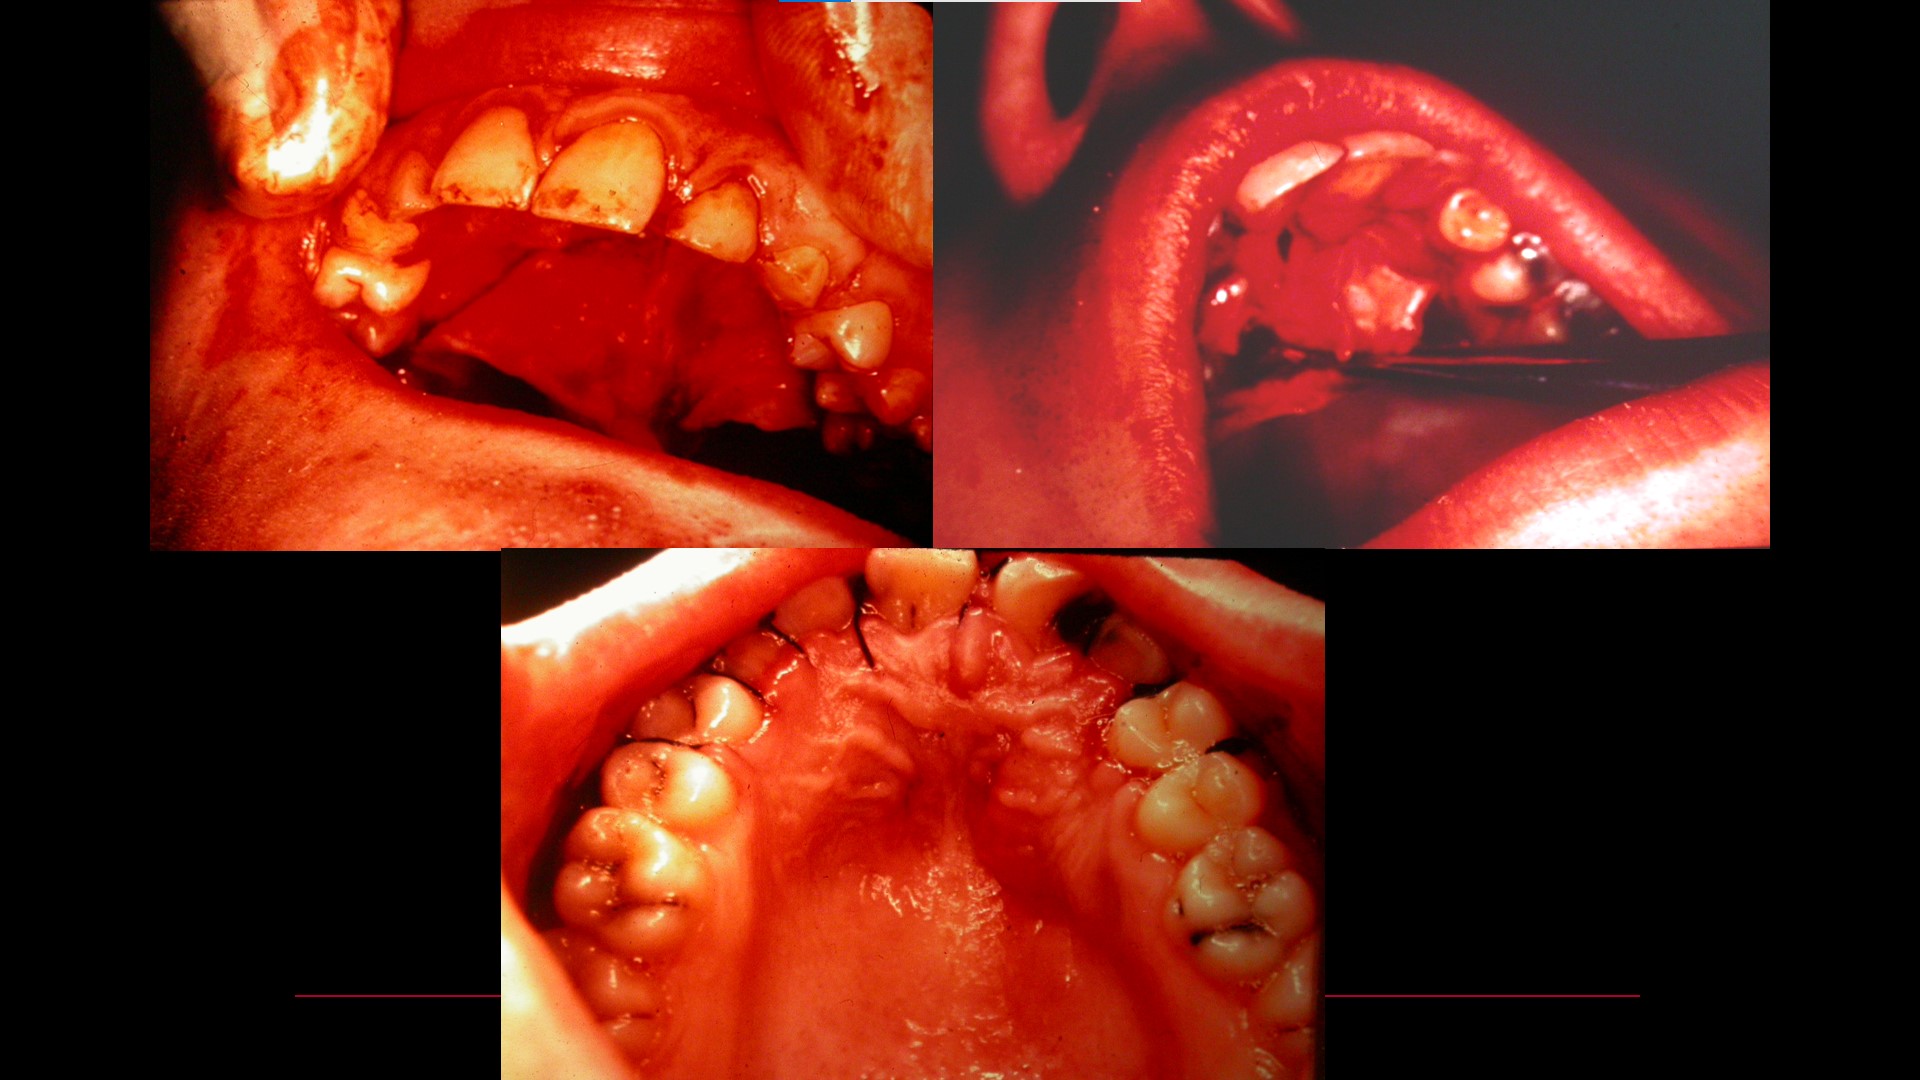

Impacted teeth